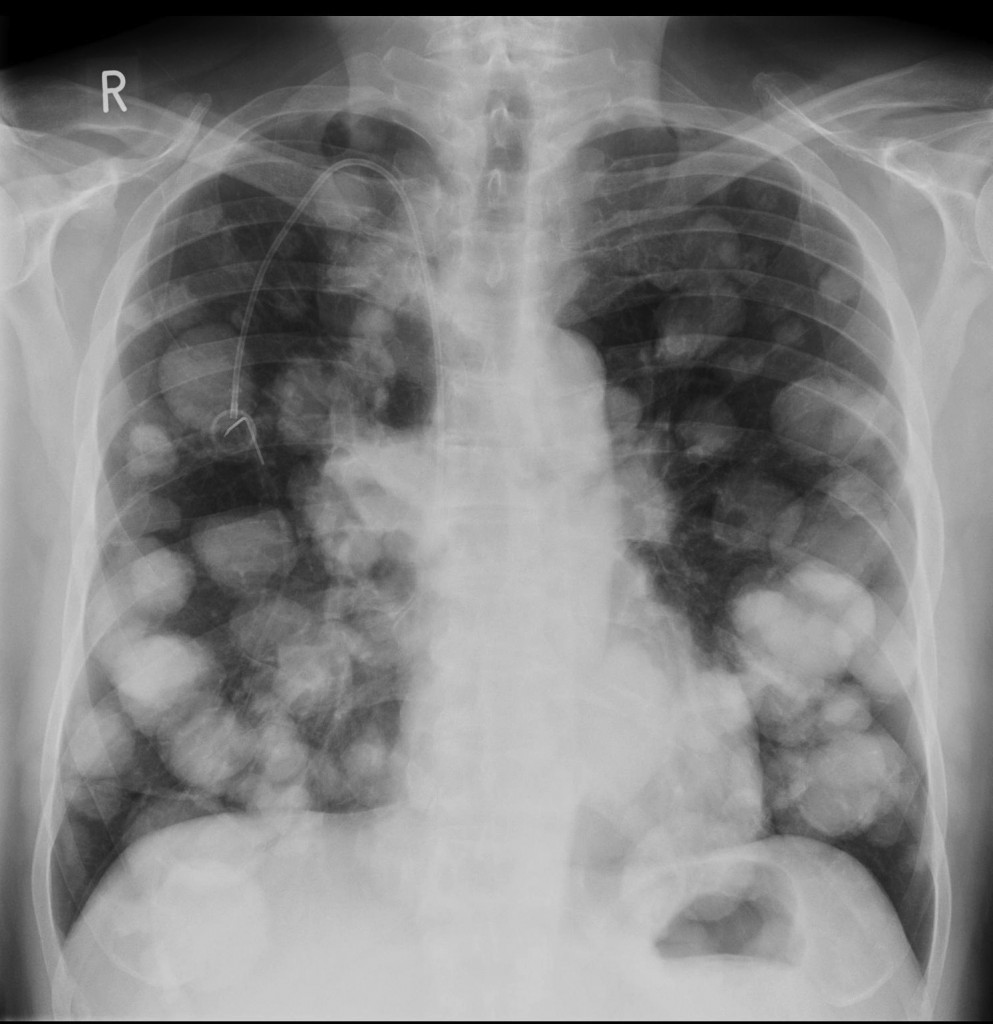

Describe the abnormality/ies

Cannonball metastases (most commonly from renal cell carcinoma)